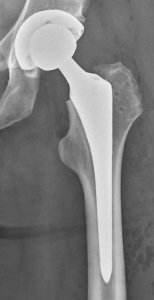

PROFILE TRAINING AND PRESENTATION Dr. Niranjanan Recieving Diploma SICOT degree in Rome, Italy Dr. Niranjanan being awarded fellowship certificate at Indian spinal injuries centre CLIINIC SOME OF Dr. NIRANJANAN's CASES